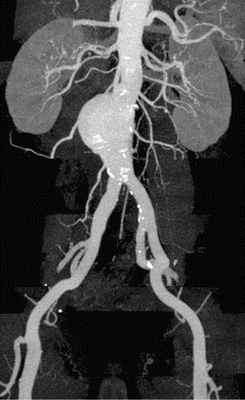

Одним из наиболее достоверных методов диагностики всей аорты является аортография. Этот метод в режиме реального времени позволяет увидеть дефекты стенок аорты, образовавшийся в результате расслоения вторичный просвет и полость аневризмы. Если же место надрыва закрылось тромбом, то аортография может дать ложноотрицательный результат.

Этот недостаток может быть устранен после выполнения компьютерной томографии с контрастированием сосудов, которую можно выполнить в К+31.

4. Ангиография (аортография) – является инвазивным методом исследования, позволяющим при помощи контраста визуализировать аорту и ее ветви. Этот метод обладает высокой диагностической ценностью, однако недостатком его является инвазивность (прокол сосуда), рентгеновское излучение, а также введение контраста, который может быть противопоказан при хронической почечной недостаточности;

5. МРТ, КТ аорты – является «золотым стандартом» диагностики аневризмы аорты и ее осложнений. Является дорогостоящим методом исследования и проводится в специализированных центрах.